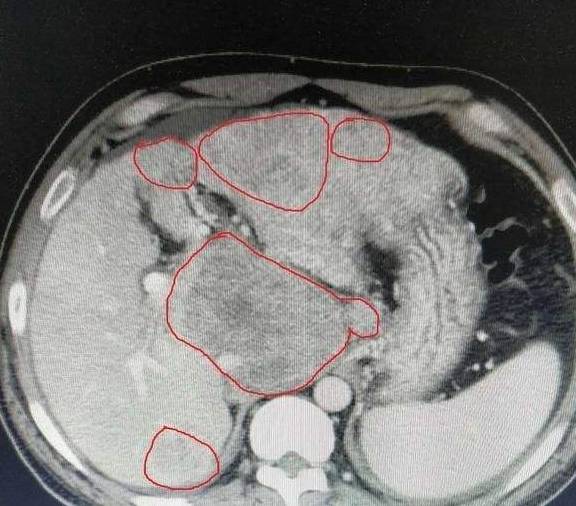

小程决定去医院检查一下 , 到达医院后 , 小程便去做了全身检查 , 身体其他指标都正常 , 但肝功能显示异常 , 进一步检查后 , 确诊肝硬化 , 并且已经到了较为严重的地步了 , 医生说:还好你来的及时 , 病情没有继续发展 , 久拖很容易导致肝脏癌变 。